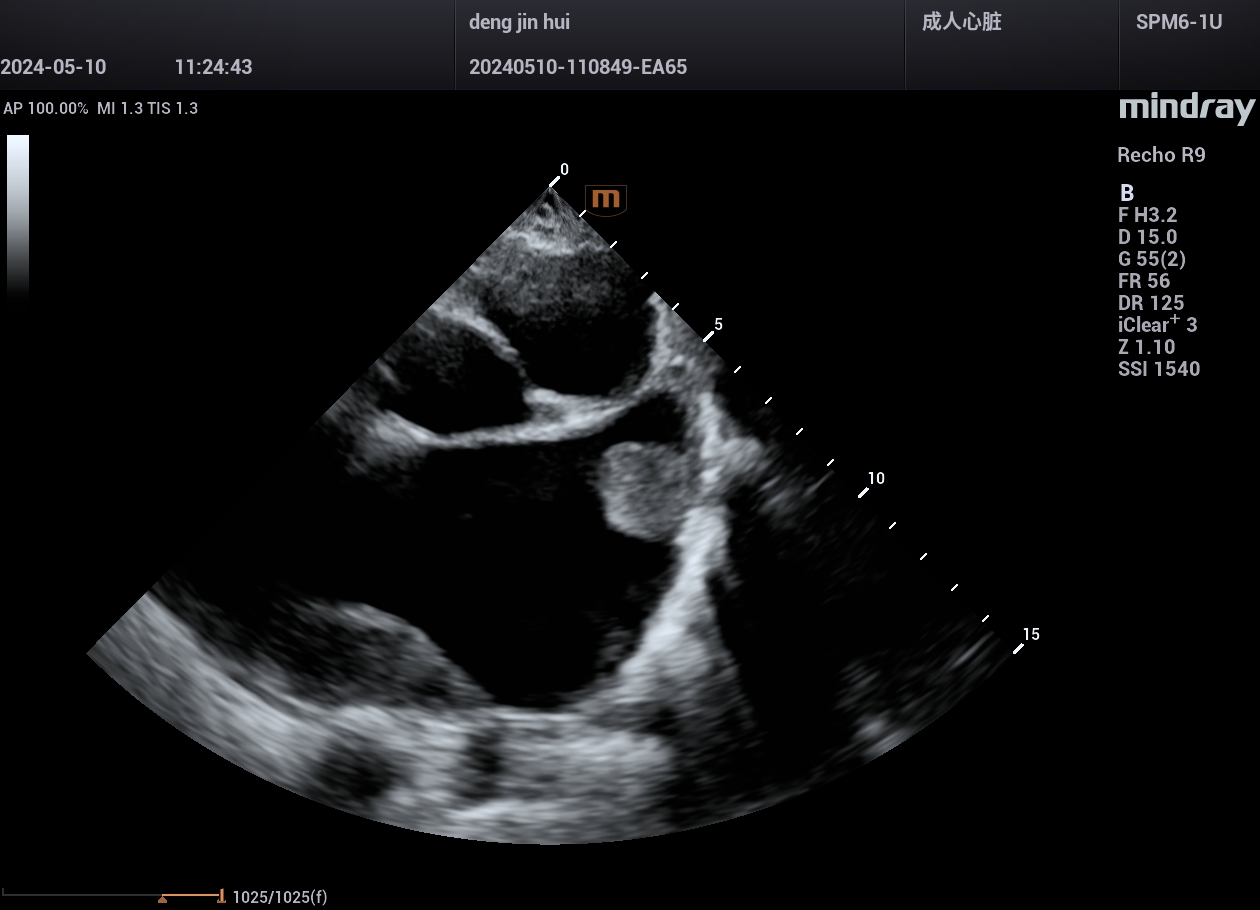

病例,主动脉瓣置换术,有瓣周漏,中山一院广西医院,2024年5月

www.jinrichaosheng.com